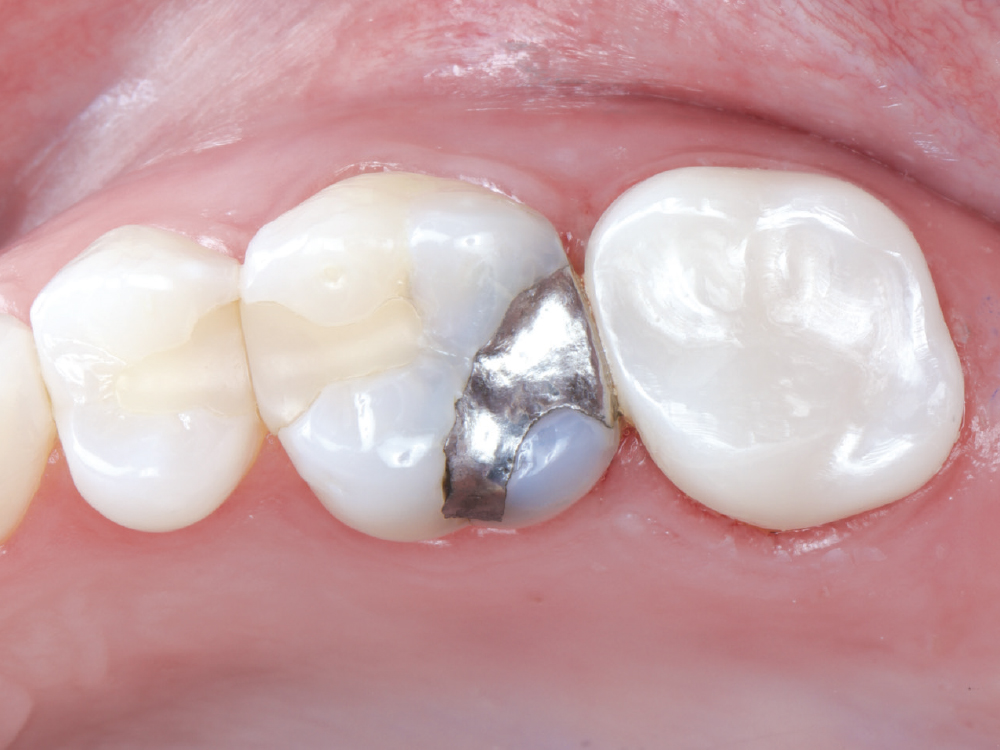

Even though she is a dental hygienist, Nikole decided to wait it out when she was told her crown on tooth #15 had an open margin. But over time, she noticed the area started to shred her floss. That’s when she decided it was time for the crown to be replaced.

Because the patient had high expectations for her restoration, I selected a BruxZir® Esthetic NOW Posterior Milling Block for its combination of esthetics and strength. Though BruxZir Esthetic was originally developed with the anterior in mind, with a yttria content that enhances the overall translucency and color, the material still maintains an excellent flexural strength of 870 MPa, meaning it is sufficiently strong enough to be used anywhere in the arch.